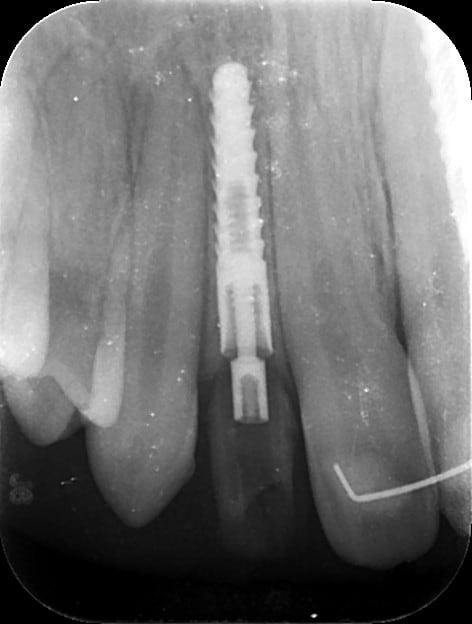

dommage j'ai oublié de prendre mes radios d'un ptit cas clinique fait vendredi...12/22 agénésies et il fallait vraiment viser juste pour éviter les racines des dents adjacentes...et être pile pour pouvoir faire les couronnes provisoires transvissées...

je ne devais pas avoir plus d'un demi mm et 1° de marge d'erreur possible pour ces 2 implants...

je posterai les images du scan et les radios post op du cas dont je viens de parler mardi ou mercredi, c'est quand même intéressant de voir ce que l'on arrive à faire avec et avoir comme précision...je n'ai presque pas décollé (petites incisions crestales en W pour aménager les futures papilles), posé les implants et réalisé les 2 couronnes prov transvissées en une petite heure seulement...

je mets les coupes et les radios post op...

intervention "quasi" flaless, juste des incisions crestales en W pour manager les papilles...

Plc12 hhx60b - Eugenol

Pl12 u0n8gy - Eugenol

Plc22 trdesx - Eugenol

Pl22 on1tll - Eugenol

Pl1222 zuoj0h - Eugenol

12 xdpxmw - Eugenol

22 w4rsbx - Eugenol

très honnêtement c'est bien mais je ne vois absolument pas pourquoi il faut guider l'instrument dans un cas comme ça, car pour la latéralité, tu suis les axes des autres dents, avec précautions ok mais bof, et pour l’épaisseur, c'est un boulevard

j'ai fais ça à main levée, et c'est tout simplement à la porté de tout praticien consciencieux, ce qui n'enlève rien au coté intéressant de ton outil.

c'est un boulevard en épaisseur, ok...

l'intérêt...c'est qu'en une petite heure c'était plié, provisoires inclues...et sans ouvrir grand pour contrôler les proximités radiculaires et faire radio sur radio de contrôle pour ne pas toucher aux racines...